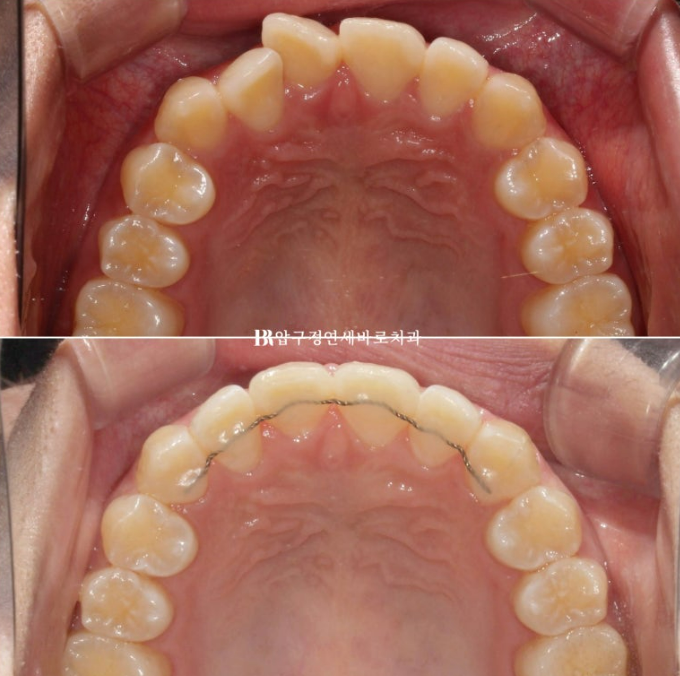

유지장치까지 붙은 모습입니다.

전 후 비교 보겠습니다.

토탈 치료기간은 6개월입니다.

23.12~24.06